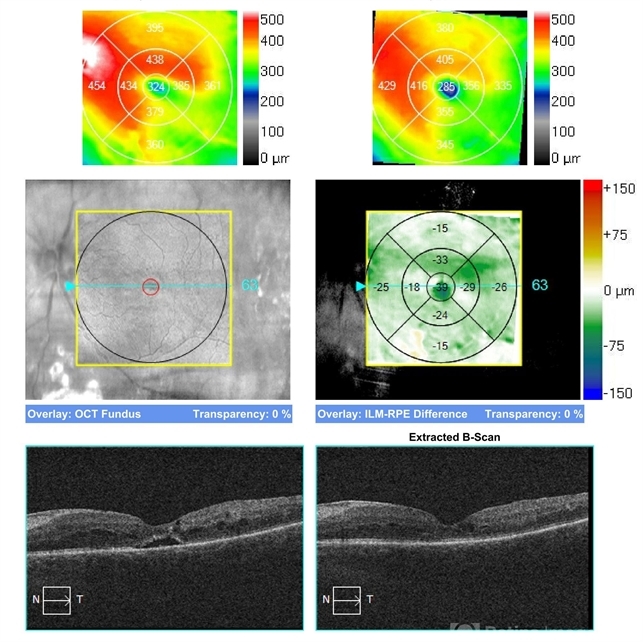

- Diabetic TRD

- Condition/keywords

- tractional retinal detachment, diabetic traction detachment

- 3 and 6 m post-op 2 avastins 20/300 at 6 months c 3+NSC